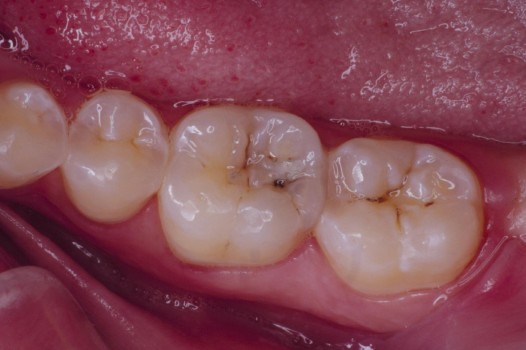

The pits and grooves on the biting surface of teeth often serve as plaque traps and pathways for bacteria to invade the inside of a tooth. This, in turn, leads to the development of cavities. Early diagnosis and treatment arrests the spread of decay and thus prolongs the life of the tooth. Regardless of the size of the affected tooth structure, decay may be swept away with the air abrasion technique and corrected by bonded ceramics, which seal the tooth against further bacterial invasion.